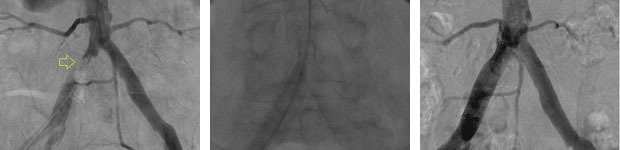

Femoral Artery Angioplasty: Significant arterial stenosis (narrowing) pre-treatment on diagnostic angiogram [left]. Angioplasty balloon inflated at across stenosis [centre]. Post-treatment image demonstrating much improved bloodflow [right]

Initially, the true extent of PAD is confirmed with detailed pictures obtained by injecting contrast directly into the arterial tree (‘angiography’). Following this, the narrowed/blocked vessel segment is crossed with a wire over which a balloon is advanced and inflated at the site of disease to widen/re-canalise the native artery (‘angioplasty’). Angioplasty is sometimes supplemented with deployment of a metal scaffold in order to hold the treated artery open (‘stenting’).